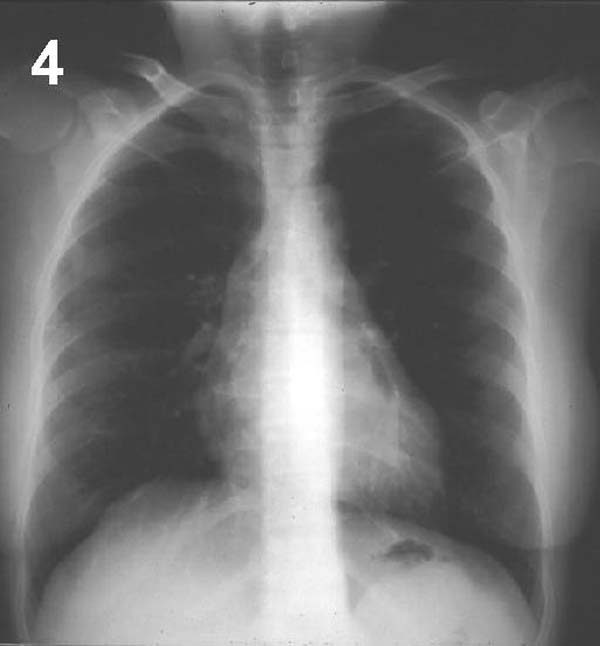

Prosiga su análisis con la siguiente placa.